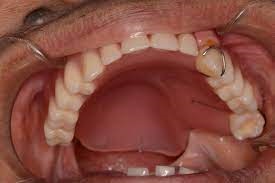

Palatal Obturator

A palatal obturator prosthesis is a type of dental appliance that is used to close a cleft palate. The prosthesis is custom-made to fit the individual's mouth and is worn to help improve speech, and swallowing, and to prevent food from entering the nasal cavity. It is typically made of acrylic and may include a metal framework to help hold it in place. The prosthesis is removable and may need to be adjusted or replaced as the individual grows and their cleft palate is repaired.